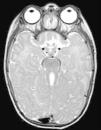

El primer caso es una lactante mujer de 6 meses con retraso psicomotor e hipotonía axial, nistagmo vertical y movimientos oculares erráticos. Prenatalmente se sospechó hipoplasia del vermis cerebeloso. En la RM cerebral posnatal se objetivó ausencia completa de vermis cerebeloso con alteración de pedúnculos cerebelosos y cuarto ventrículo con morfología «signo del molar» (fig. 1). El síndrome de Joubert (OMIM 213300) se confirmó al detectar la mutación c.2168G>A (pArg723Gln) en el gen AHI1 en homocigosis. Se caracteriza por malformación congénita de tronco cerebral y agenesia o hipoplasia vermis cerebeloso, que causa hipotonía y ataxia, retraso desarrollo motor, nistagmo y patrón respiratorio neonatal de taquipnea/disnea. El déficit intelectual es variable. Puede asociar distrofia retiniana, nefronoptisis y polidactilia, presentes en otras ciliopatías. Su herencia es autosómica recesiva, identificando mutaciones en distintos genes: AHI1, NPHP1, CEP290, TMEM67, RPGRIP1L, ARL13B y CC2D2A5. El síndrome de Bardet-Biedl, Meckel-Gruber, la amaurosis congénita de Leber y la nefronoptisis comparten mutaciones en gen CEP290, demostrando la superposición genética y clínica en los síndromes asociados a disfunción del cilio primario6.